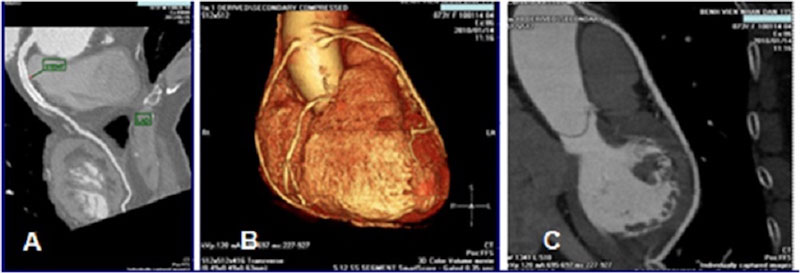

Chụp MRI tim được thực hiện để phân tích toàn diện về cấu trúc, chức năng và các bệnh của tim. Ngoài các lý do chẩn đoán ở trên, có những thời điểm khác bạn có thể cần chụp MRI tim, bao gồm:

- Kiểm tra tình trạng tổn thương tim sau cơn đau tim hoặc những vùng thiếu máu do tắc nghẽn động mạch tim.

- Xác định vị trí mà bác sĩ cần điều trị trong quá trình cắt bỏ.

- Lập kế hoạch cho việc điều trị tim của người bệnh.

- Đánh giá sự thành công của một ca phẫu thuật gần đây.

- Kiểm tra xem rối loạn đã ảnh hưởng đến tim.

Chụp MRI được thực hiện để phân tích toàn diện về cấu trúc, chức năng và các bệnh của tim.